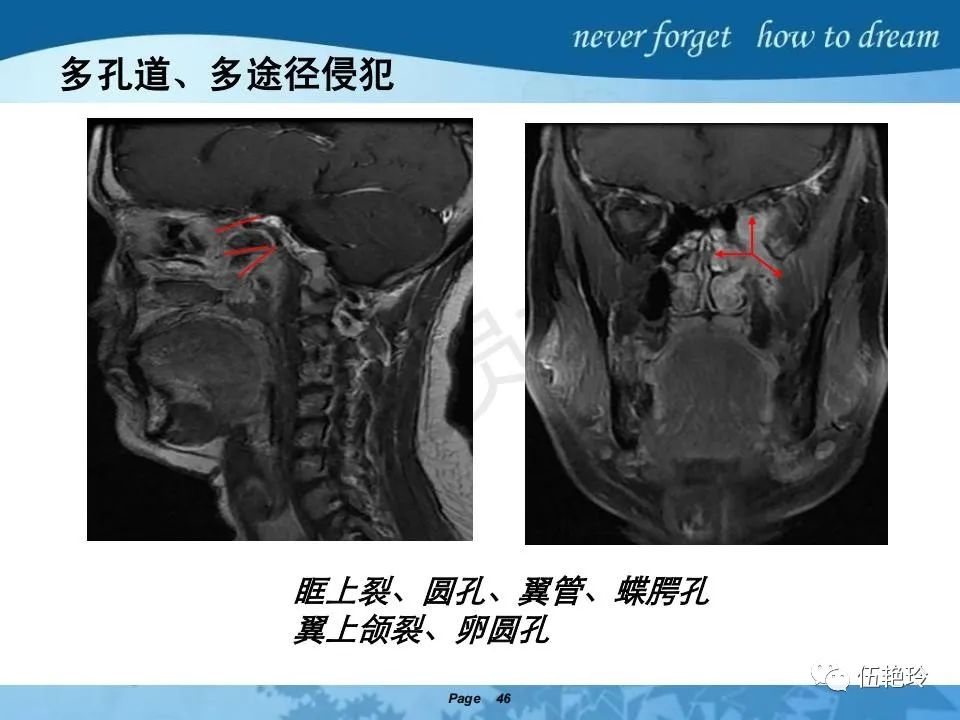

2.2 鼻咽特有的解剖途径:鼻咽癌原发灶循序进展的总途径:鼻腔(47.8%)→翼腭窝(15.2%)→ 眶下裂(3.2%)→眶尖(1.2%)→海绵窦(0.6%)。

2.31 向上颅内:①鼻咽顶壁→破裂孔(岩尖、斜坡)→蝶窦、海绵窦;②鼻咽顶壁→蝶骨基底部→蝶窦、海绵窦;③鼻咽侧壁→茎突前间隙→蝶骨大翼(卵圆孔)→海绵窦;④鼻咽侧壁→茎突前间隙→翼腭窝→ 颞下窝;⑤鼻咽前壁→鼻腔→翼突、翼腭窝→眶下裂→眶尖→海绵窦;⑥鼻咽前壁→鼻腔→上颌窦、筛窦;